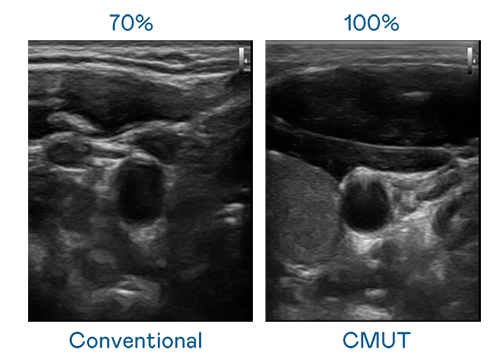

CMUT 技术是一种用电容式微机电元件来产生超音波讯号的技术。与传统 PZT 压电式技术相比,CMUT 频宽增加 30%,更宽频的超音波讯号让影像解析度大幅提升,是实现高影像品质医疗超音波扫描、促进精准医疗发展的关键技术。

大频宽带来超清晰影像

超音波影像的解析度高低,首先取决于探头能发出的讯号频宽。ibet CMUT 可提供高清晰的超音波讯号,提供高频宽、高灵敏度、影像纹理细节更高的超音波影像,协助医护人员缩短影像判读时间及利用精准的医疗影像进行诊断。